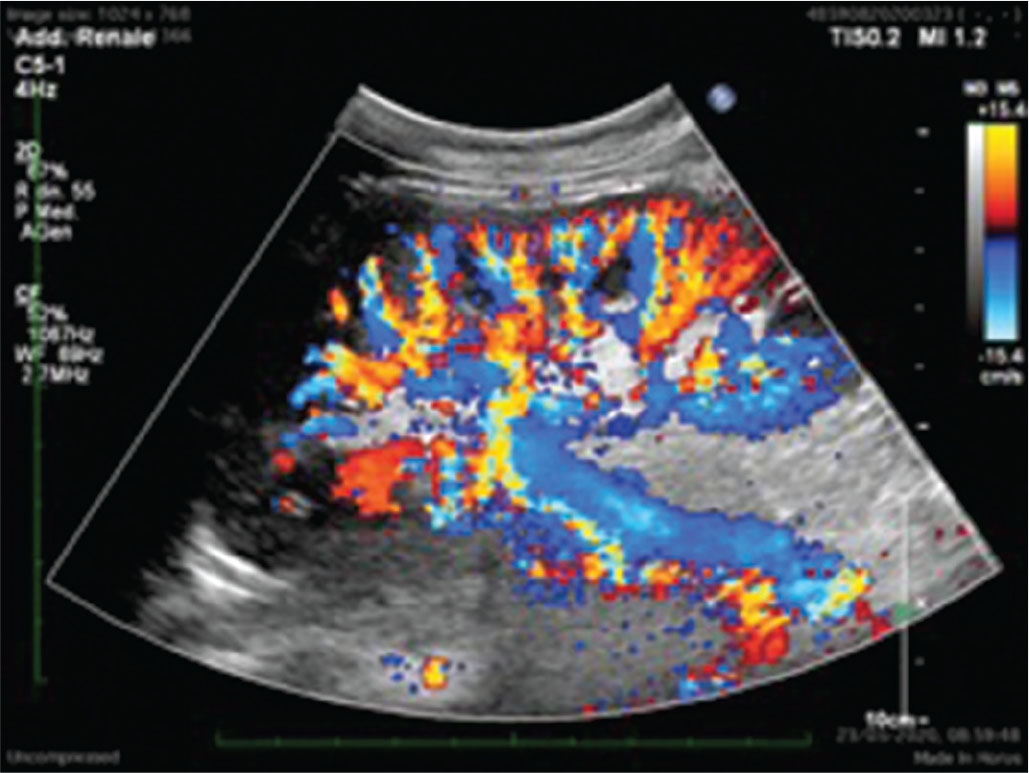

Qualsiasi tipo di nefropatia, sia essa primariamente parenchimale, vascolare o urologica, in fase terminale determina il fallimento del TR. Il trapianto renale non funzionante solitamente viene lasciato in situ. L’ERT è importante anche una volta che il trapianto è fallito. È essenziale praticare un monitoraggio stretto delle caratteristiche ecografiche del TR nel corso della progressiva riduzione della terapia immunosoppressiva e, ancora, nel follow-up a lungo termine. Rigetti acuti possono manifestarsi e possono rendersi particolarmente pericolosi anche per la vita del paziente, così come, nel lungo temine, lesioni neoplastiche possono svilupparsi sul rene trapiantato ormai non più funzionante. Dal punto di vista ecografico, il rene trapiantato cronico e non funzionante non ha caratteristiche dissimili da quelle di un rene nativo non funzionante: infatti, le dimensioni si riducono progressivamente, viene completamente alterata la differenziazione cortico-midollare e si osserva una globale riduzione della vascolarizzazione intraparenchimale. Spesso si possono presentare degenerazioni cistiche anche particolarmente estese (soprattutto dopo molto tempo dalla ripresa della terapia sostitutiva) e il parenchima può essere sede anche di calcificazioni estese (Fig. 3).

(Personal image, Fondazione IRCCS Ca’ Granda Ospedale Maggiore Policlinico, Milano)